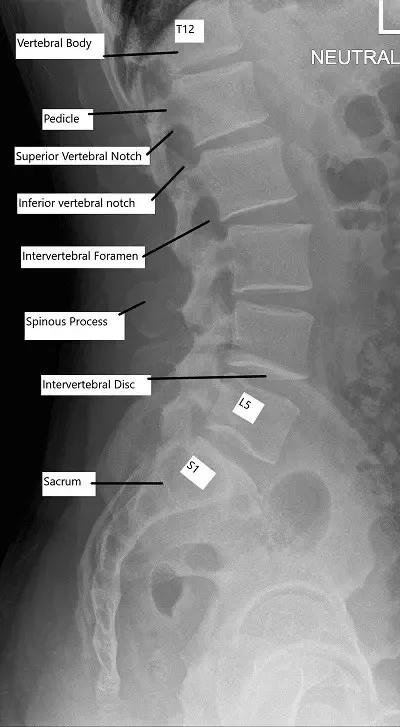

- Columna lumbar (parte inferior de la espalda): 5 vértebras (L1-L5)

La columna torácica conecta con la caja torácica. La columna lumbar está formada por grandes vértebras, ya que soporta el peso del cuerpo y conecta la parte superior del cuerpo con la pelvis.

Las radiografías proporcionan una visualización básica de la alineación de la columna vertebral y la integridad ósea. Los TAC ofrecen imágenes detalladas de las estructuras óseas y son útiles en traumatismos o afecciones degenerativas. La RM es la mejor herramienta de diagnóstico por imagen para evaluar los tejidos blandos, incluidos los discos intervertebrales, los ligamentos, las raíces nerviosas y la médula espinal.